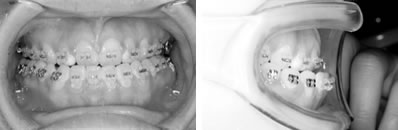

片顎のマルチブラケットで改善した9歳症例

前歯部分の凸凹は上下とも重度であった。乳歯の虫歯も多く、歯磨き練習も重要でした。